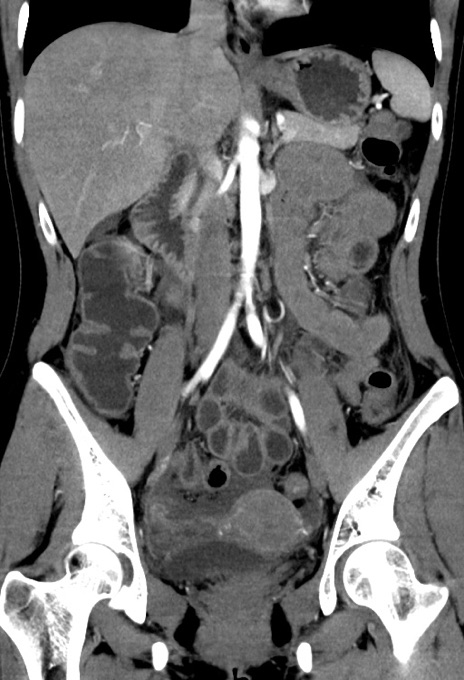

症例17(冠状断像)

【症例】20歳代女性

【主訴】嘔吐、下腹部痛

【現病歴】昨日夕食後に嘔吐し下腹部痛が出現。本日になっても嘔吐持続し改善しないため来院。

【身体所見】意識清明、BT 37.2℃、BP 108/67mmHg、腹部:平坦、やや硬、下腹部正中から右にかけて圧痛あり、反跳痛軽度あり、tapping pain(+)。

【データ】WBC 13600、CRP 14.94